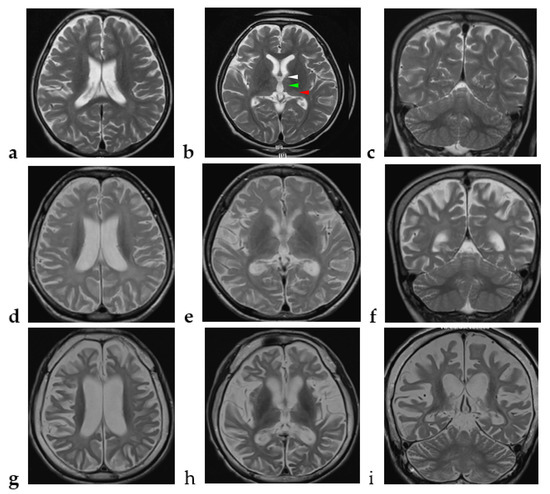

| Brain magnetic resonance imaging | |

| Supratentorial cerebral atrophy | 15 (100) |

| Cerebellar atrophy | 11 (73) |

| Diffuse white matter T2 hyperintensity | 12 (80) |

| Thalamus involvement | 2 (13) |